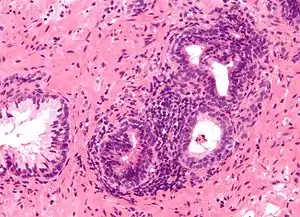

Microanatomy

The prostate consists of glandular and connective tissue.[1] Tall column-shaped cells form the lining (the epithelium) of the glands.[1] These form one layer or may be pseudostratified.[3] The epithelium is highly variable and areas of low cuboidal or flat cells can also be present, with transitional epithelium in the outer regions of the longer ducts.[9] The glands are formed as many follicles, which in drain into canals and subsequently 12–20 main ducts, These in turn drain into the urethra as it passes through the prostate.[3] There are also a small amount of flat cells, which sit next to the basement membranes of glands, and act as stem cells.[1]

The connective tissue of the prostate is made up of fibrous tissue and smooth muscle.[1] The fibrous tissue separates the gland into lobules.[1] It also sits between the glands and is composed of randomly orientated smooth-muscle bundles that are continuous with the bladder.[10]

Over time, thickened secretions called corpora amylacea accumulate in the gland.[1]

Microscopic glands of the prostate

Microscopic glands of the prostate